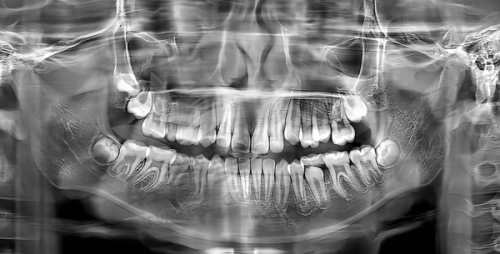

吴忠盐池县小姬口腔门诊部擅长处理各种口腔问题。其中,镶牙技术是其一大特色,得到了患者的一致好评。无论是活动假牙、固定假牙还是种植牙等镶牙方式,医生们都能根据患者的具体情况进行精细的操作,为患者修复良好的咀嚼功能和美观的牙齿外观。此外,门诊部在常见口腔疾病的治疗方面也有着丰富的经验,如龋齿的填充治疗、牙髓炎和根尖周炎的根管治疗等。对于牙周疾病,医生们会采用专精的方法进行系统的治疗,包括洗牙、刮治等,以维护患者的牙周健康。同时,门诊部还能开展牙齿美白、牙齿矫正等项目,满足患者对于牙齿美观和功能的不同需求。

吴忠盐池县小姬口腔门诊部不断更新诊疗设备,以提高医疗服务的质量和效率。配备了一些常见的精良口腔诊疗设备。例如,口腔扫描仪可以快速、正确地获取患者口腔的三维数据,为后续的治疗方案制定提供严谨的依据;根管治疗仪能够更精细地进行根管治疗,提高治疗的成功几率;数字化口腔扫描仪可以帮助医生更直观地观察患者牙齿的情况,做出更正确的诊断。此外,可能还配备了激光治疗仪等设备,用于一些特殊的口腔疾病治疗和牙齿美容项目。这些精良的仪器设备为门诊部的医疗服务提供了有力的支持。